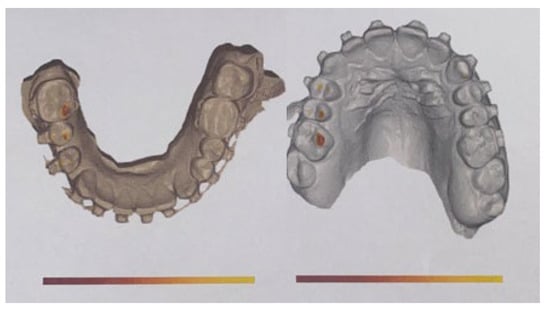

- Three-dimensional-guided and similar planning guides: Cascone et al. introduced the usage of 3D mandible and skull cast models based on CBCT to establish the best methods of surgical planning on 3D printed models [102]. The herein-mentioned planning on two cases indicates that proportional condylectomy might be used as the sole procedure for UCH treatment when detailed measurements on 3D models, either virtual or printed, are used to improve the surgical outcomes [103,104].